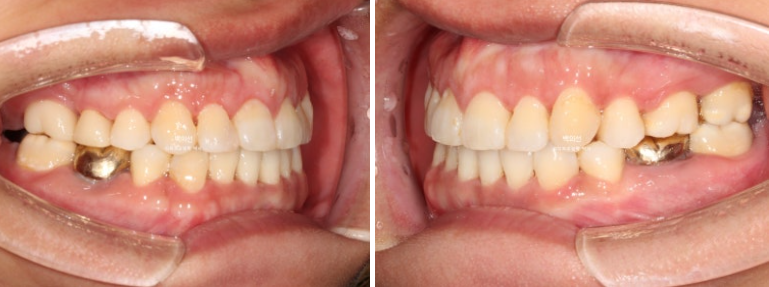

2022.12~25.06

브릿지를 잘라낸 공간은 교정으로 깔끔히 마무리 되었고 교정 중 사용한 임시치아는 교정 마무리 시점에서 흰색 크라운으로 교체되었습니다.

이제 전 후 비교 보겠습니다.

교합은 1급 교합관계를 보이며 물샐틈없이 좋습니다.

중심선을 잘 맞으며 아래턱 비대칭에 의한 반대교합은 해소되었습니다. 교정으로 턱뼈 자체를 바꿀 수는 없지만 최소한 치아중심선을 맞춰줄 수 있습니다.